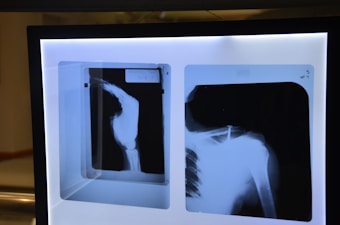

State-of-the-Art Techniques for Restored Mobility

Total Hip Replacement

Our Total Hip Replacement procedures use modern prosthetics and minimally invasive methods to relieve pain and restore full motion. We prioritize faster recovery and long-term joint performance, helping patients return to an active lifestyle with confidence.